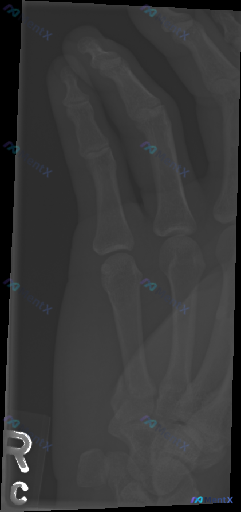

整理到一个值得讨论的影像相关情况: 病例背景 一份右手正位X光片,常规影像学评估结果如下: - 各指骨、掌骨、腕骨骨皮质连续性未见明显中断,无明确骨折线、隐匿性骨折征象或骨膜反应; - 各掌指、指间关节及腕骨间关节间隙基本正常,对位良好,无脱位半脱位; - 骨质密度分布均匀,未见明显骨质疏松、骨质硬...

整理了一份右手指部的影像+临床分析资料,觉得很适合讨论「影像阴性≠临床没事」的情况。 先给出影像的客观结论: 这份是右手指斜位X光片,影像科报告的描述是: - 各段骨皮质连续,未见明显骨折线或脱位征象 - 关节对位正常,关节间隙清晰 - 骨质密度均匀,未见骨侵蚀或增生 - 软组织轮廓自然,未见明显高...